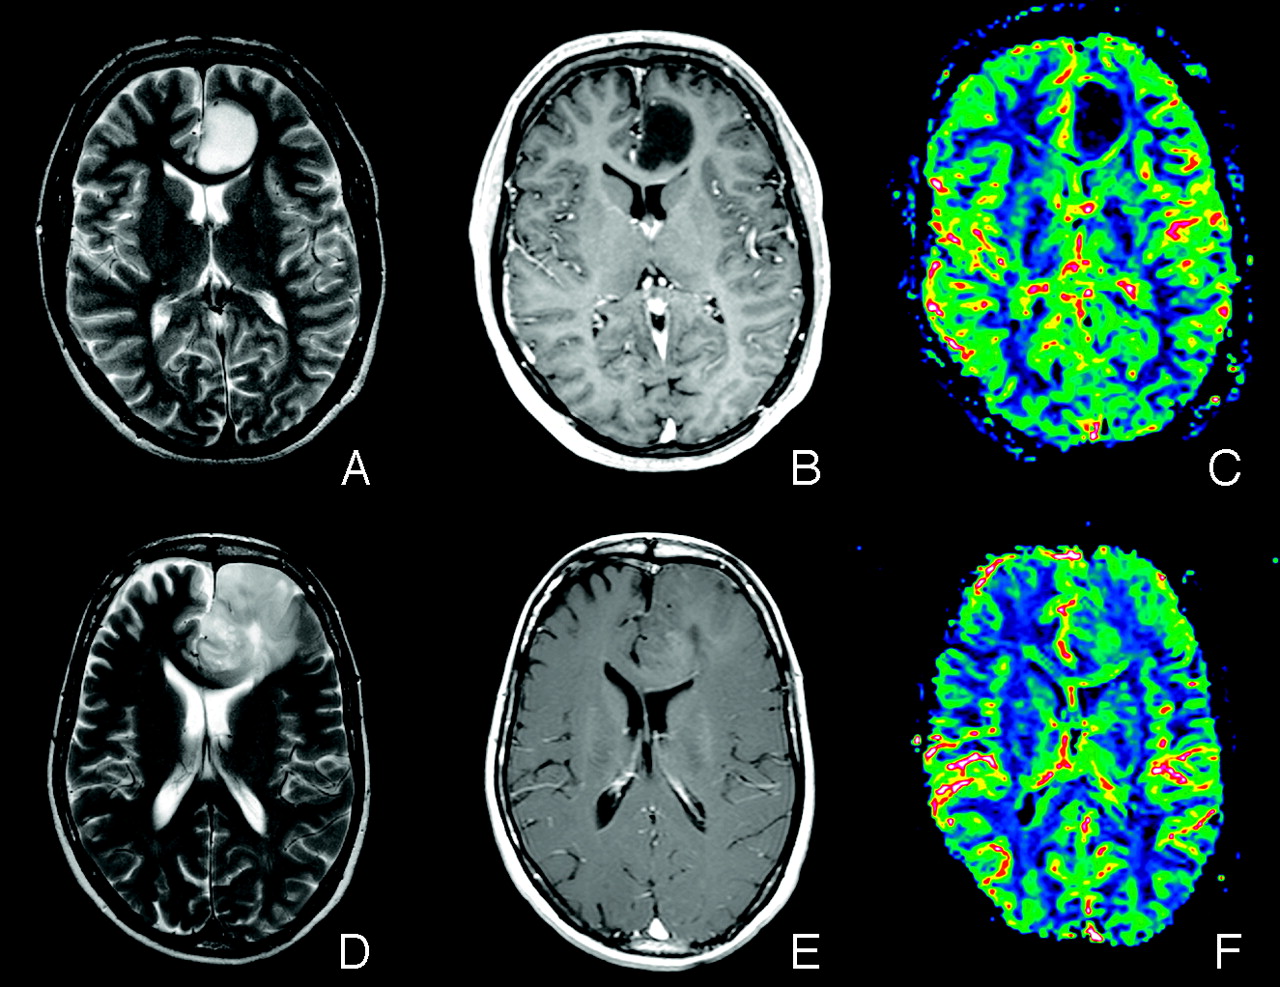

The histogram method was able to differentiate HGGs from LGGs (P < .001), high-grade from low-grade oligodendroglial tumors (P = .004), and identify low-grade oligodendroglial LOH status (P = .009). The corresponding ICC values were 0.902, 0.918, and 0.801, respectively. Figure 1 shows conventional MR images with coregistered rCBV maps of low-grade oligoastrocytomas with and without LOH on 1p/19q. The resulting histograms from the 2 low-grade oligoastrocytomas are shown in Fig 2. A plot of the mean histogram peak heights with SEs for the different glioma types investigated is shown in Fig 3. A scatterplot of the 52 histogram peak heights is shown in Fig 4.

A, Axial T2-weighted fast spin-echo (FSE) image (TR/TE, 4000/104 ms) of a patient (subject 3) with a low-grade oligoastrocytoma without LOH on 1p/19q. B, Axial postcontrast T1-weighted spin-echo (SE) image (TR/TE, 500/7.7 ms) of subject 3. C, Coregistered rCBV map of subject 3. D, Axial T2-weighted FSE image (TR/TE, 4000/104 ms) of a patient (subject 7) with a low-grade oligoastrocytoma with LOH on 1p/19q. E, Axial postcontrast T1-weighted SE image (TR/TE, 500/7.7 ms) of subject 7. F, Coregistered rCBV map of subject 7. Note the low rCBV values in the tumor area in image C compared with the tumor area in image F, typical of low-grade oligodendroglial tumors without LOH on 1p/19q. The corresponding normalized histogram signatures are shown in Fig 2.